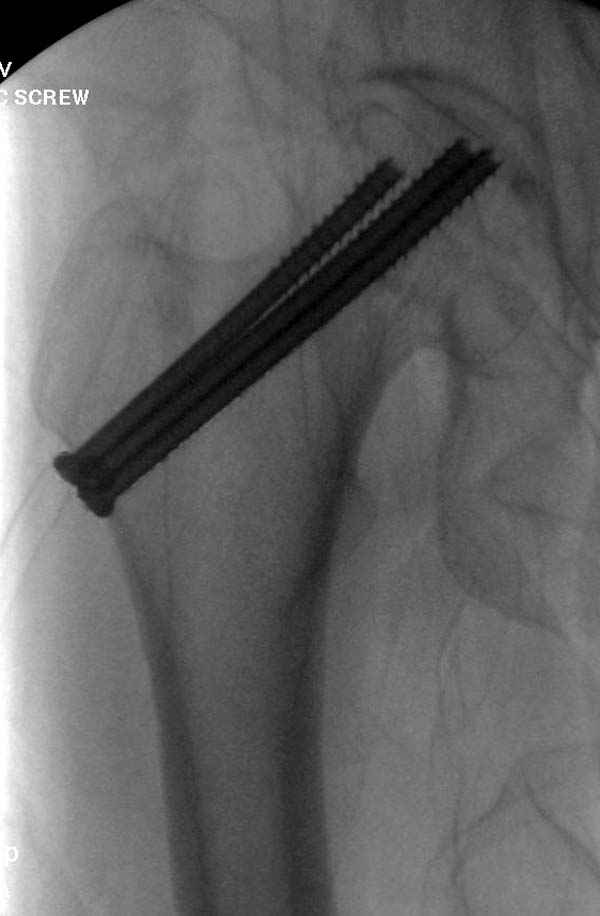

Профилактику дальнейшего раскола неполного перелома шейки провели тремя канюлированными шурупами.

На второй день после выписки упал дома. Снимки приложены. Коллеги рекомендуют удаление шурупа и вытяжение. Что делать?